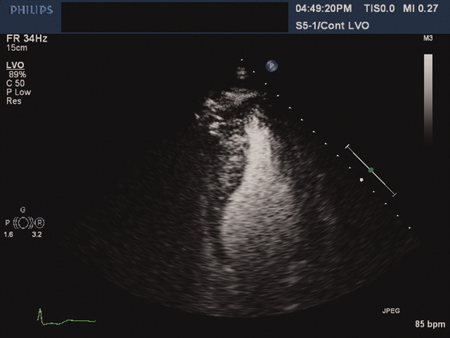

Cardiomiopatia hipertrófica apical: vista ecocardiográfica de 4 câmaras com contraste

Ahmed I, Smalley SJ, Zhu DWX, et al. Sudden cardiac arrest in apical hypertrophic cardiomyopathy. BMJ Case Reports. 2009;doi:10.1136/bcr.04.2009.17